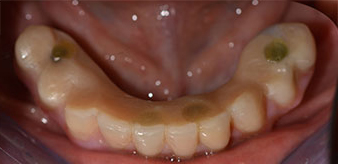

È stata eseguita una tomografia computerizzata Dentale Cone Beam in 3D (CBCT, con Planmeca) per aiutare la programmazione dell'intervento e la riduzione di rischi. L'esame ha evidenziato che la qualità e quantità dell'osso disponibile era sufficiente per eseguire l'intervento e la ricostruzione immediata, utilizzando il metodo Fast & Fixed. In base al protocollo del sistema, gli impianti sono stati inseriti in posizione 35, 32, 42 e 45. Gli impianti distali vengono installati a un angolo massimo di 45 gradi. Così facendo, il profilo che ne risulta viene spostato in posizione posteriore, generando un poligono di supporto più ampio (Fig. 3).